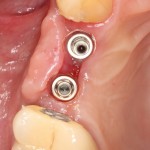

Делаем разрез, смотрим, что там с имплантами. А с ними всё в порядке:

Как и с окружающей их костной тканью:

Обратите внимание, до какого уровня имплантат находится в костной ткани. До полированной фаски — и это правильное расположение и глубина погружения XiVE. У разных имплантационных систем они могут отличаться — см. инструкцию.

Мы ставим формирователи десны: